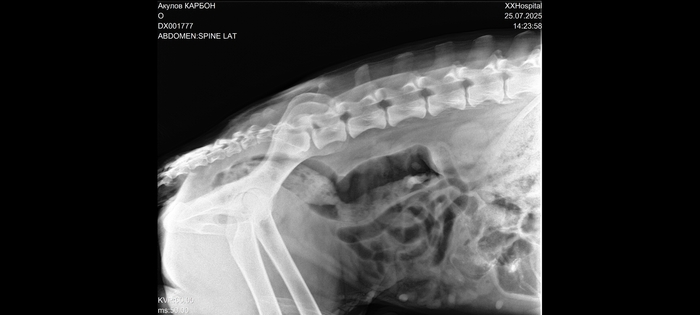

Немецкая овчарка 7лет. Отказали задние лапы

За 5 дней у собаки отказали задние лапы .

1 день. Вечером не хотел гулять. Пройдет 50 метров, сядет - " Не пойду дальше". Аппетита нет.

2 день. Заметил что начали заплетаться задние лапы и неустойчивая походка. Поел.

3 день. Начал с трудом вставать. Погуляли, вроде расходился. Лапы так же заплетаются. Аппетит хороший.

4 день. Еле встал, вообще никуда идти не захотел.

5. день. Больше на задние лапы не вставал. Поехали в 1 клинику, сделали УЗИ брюшной полости. В пределах нормы. Сказали что мочевой пузырь переполнен потому, что он лапу поднять не может. Я сразу понял, что там за специалисты. Даже не объяснили, что нужно катетер ставить - это нам уже во второй клинике сказали. Ветеринар по этому поводу ругалась сильно. Научили ставить катетер (сам он сходить не может).

Болевая чувствительность ниже ребер отсутствует, при этом щекотку чувствует и даже задними лапами дёргает, когда пузо чешешь.

Сделали рентген и анализ крови.

Заключение - проблемы в позвоночнике.

Здесь правда Карбон по моложе.